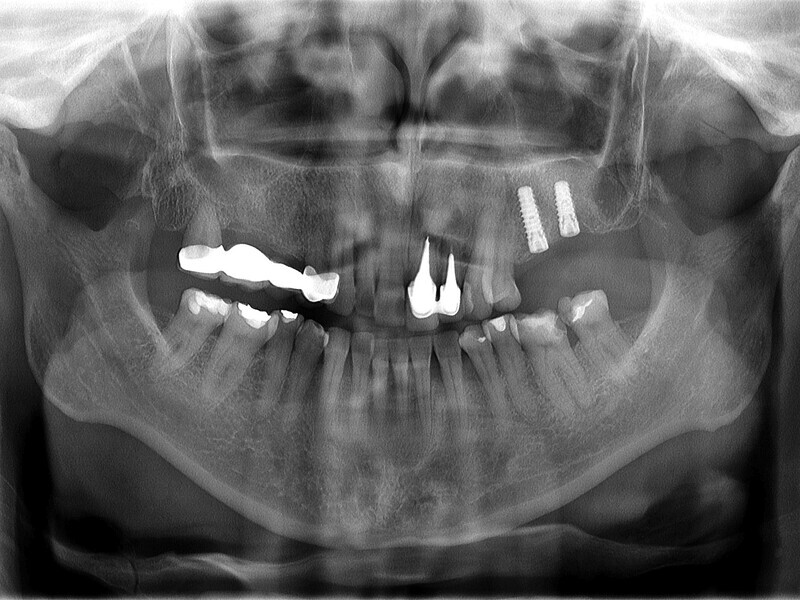

Fig. 11: Panoramic finding after six months of uneventful healing.